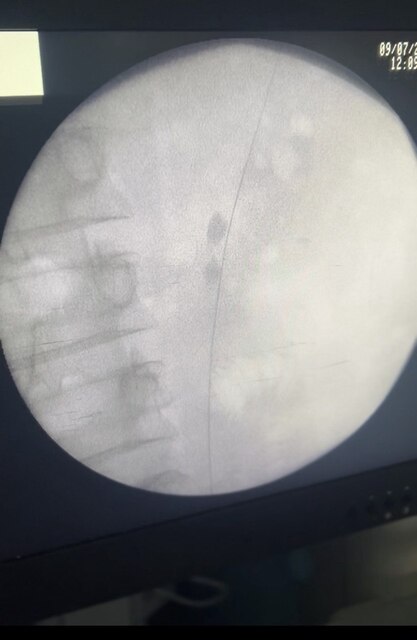

В урологічному центрі Центральної міської клінічної лікарні м. Суми активно застосовується перкутанна нефролітотрипсія — один з найбільш ефективних і безпечних методів лікування складних випадків сечокам’яної хвороби.

Це сучасна ендоскопічна операція, яка передбачає прокол у ділянці попереку, через який за допомогою спеціального інструменту в нирці роздрібнюють і видаляють камені. Такий підхід дозволяє уникнути хірургічних розрізів і значно скорочує період відновлення пацієнта.

У Центральній міській клінічній лікарні м. Суми цей метод застосовується як при одиничних каменях, так і при складних клінічних випадках сечокам’яної хвороби. Фахівці мають необхідну підготовку, обладнання та досвід, щоб надати якісну урологічну допомогу пацієнтам із різних куточків області та країни.